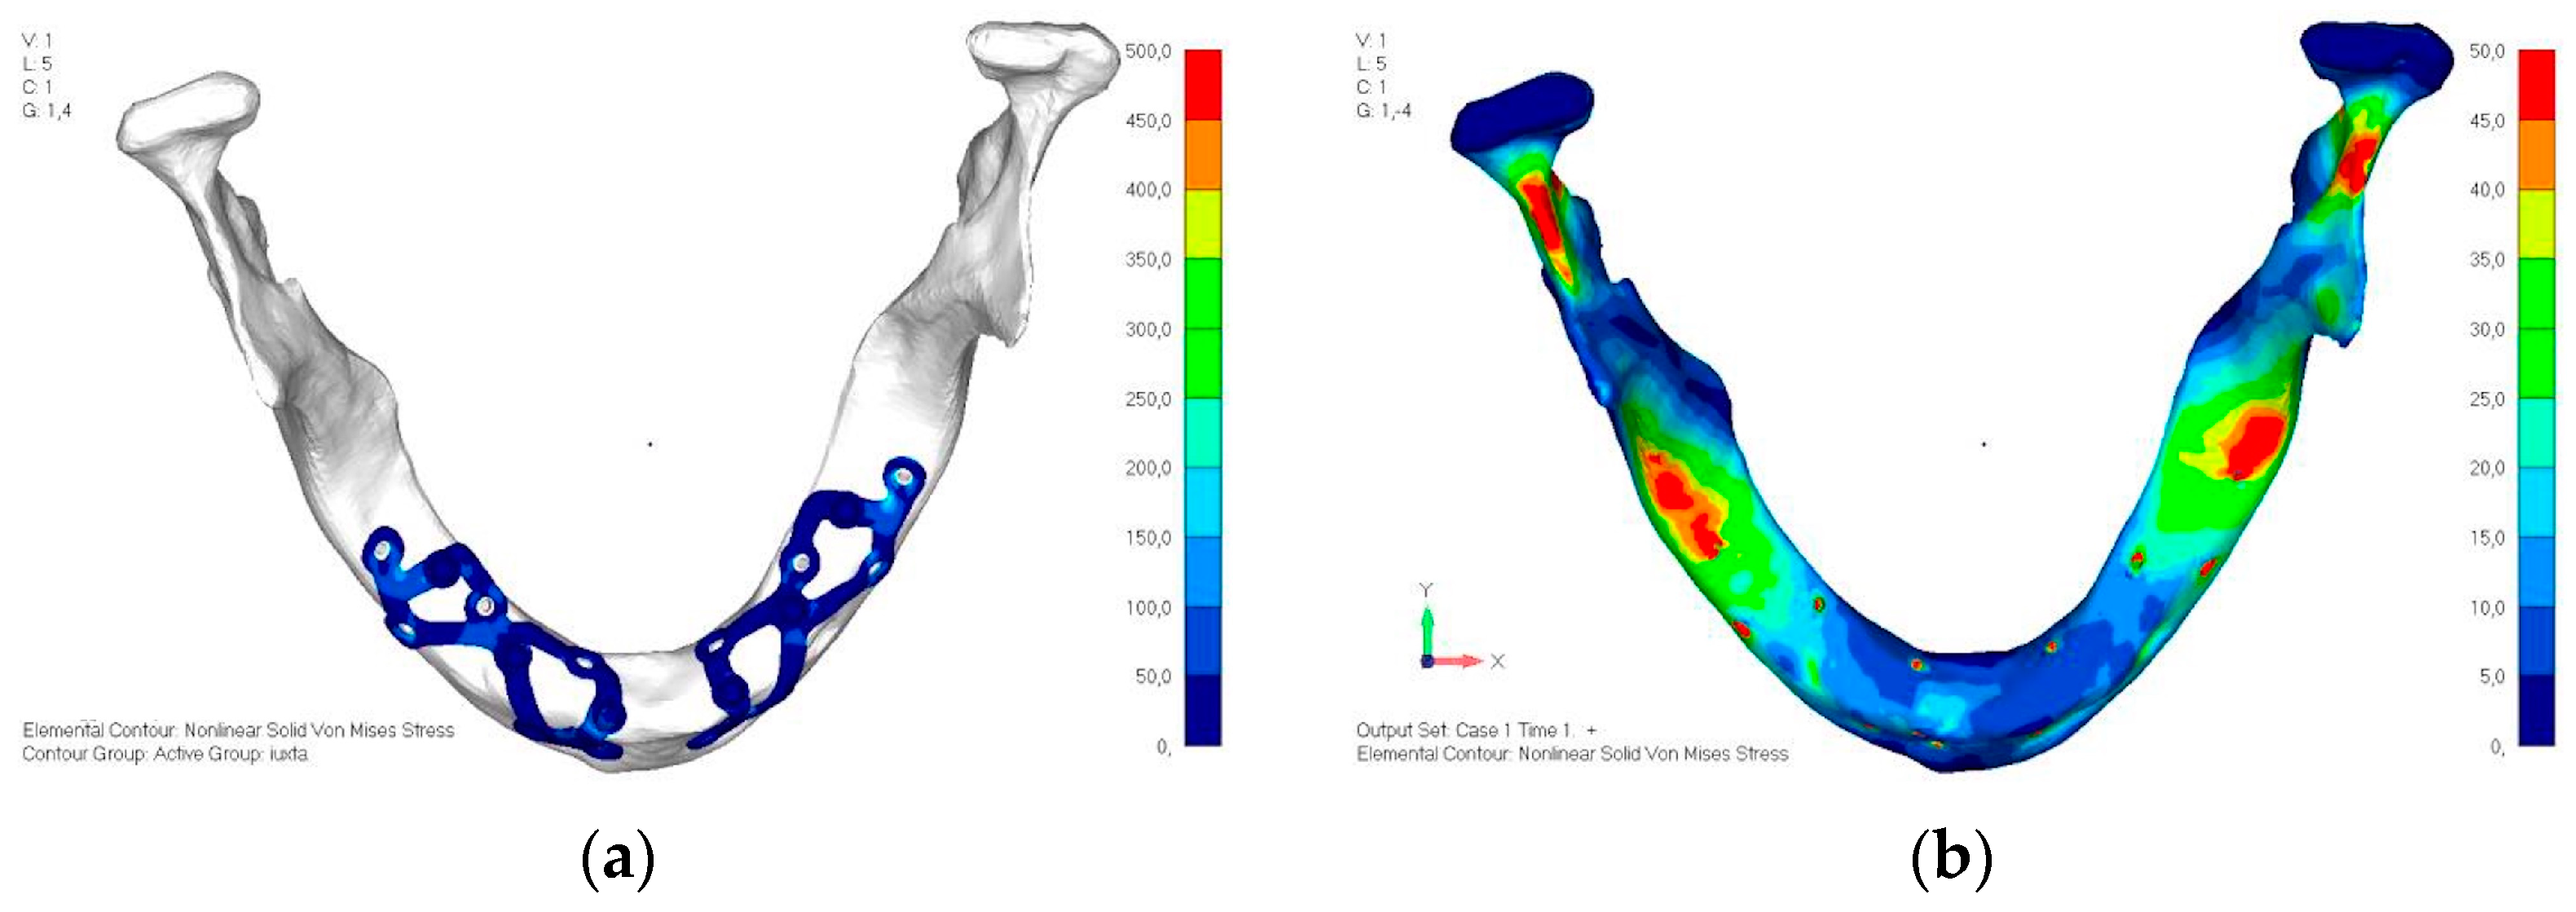

- Model V3. To reduce the load on the front screws, it was decided to add an additional screw, distributing the load of the anterior abutment across three screws instead of two (Figure 27). The addition of the anterior screw has certainly improved the distribution of stresses, as the volume of material experiencing stresses greater than 50 MPa near the screws has decreased (Figure 28a,b).

- Model V4. This version was derived from version 3 by adding a screw in the posterior sector, positioned in the vestibular direction (Figure 29). Again, the addition of an anchoring screw has allowed for more effective distribution of the stresses. The posterior alveolar area, particularly around the more posterior screws, remains notably stressed (Figure 30a,b). However, this phenomenon is attributed to the geometry and configuration of the bone rather than the presence of a cortical screw.